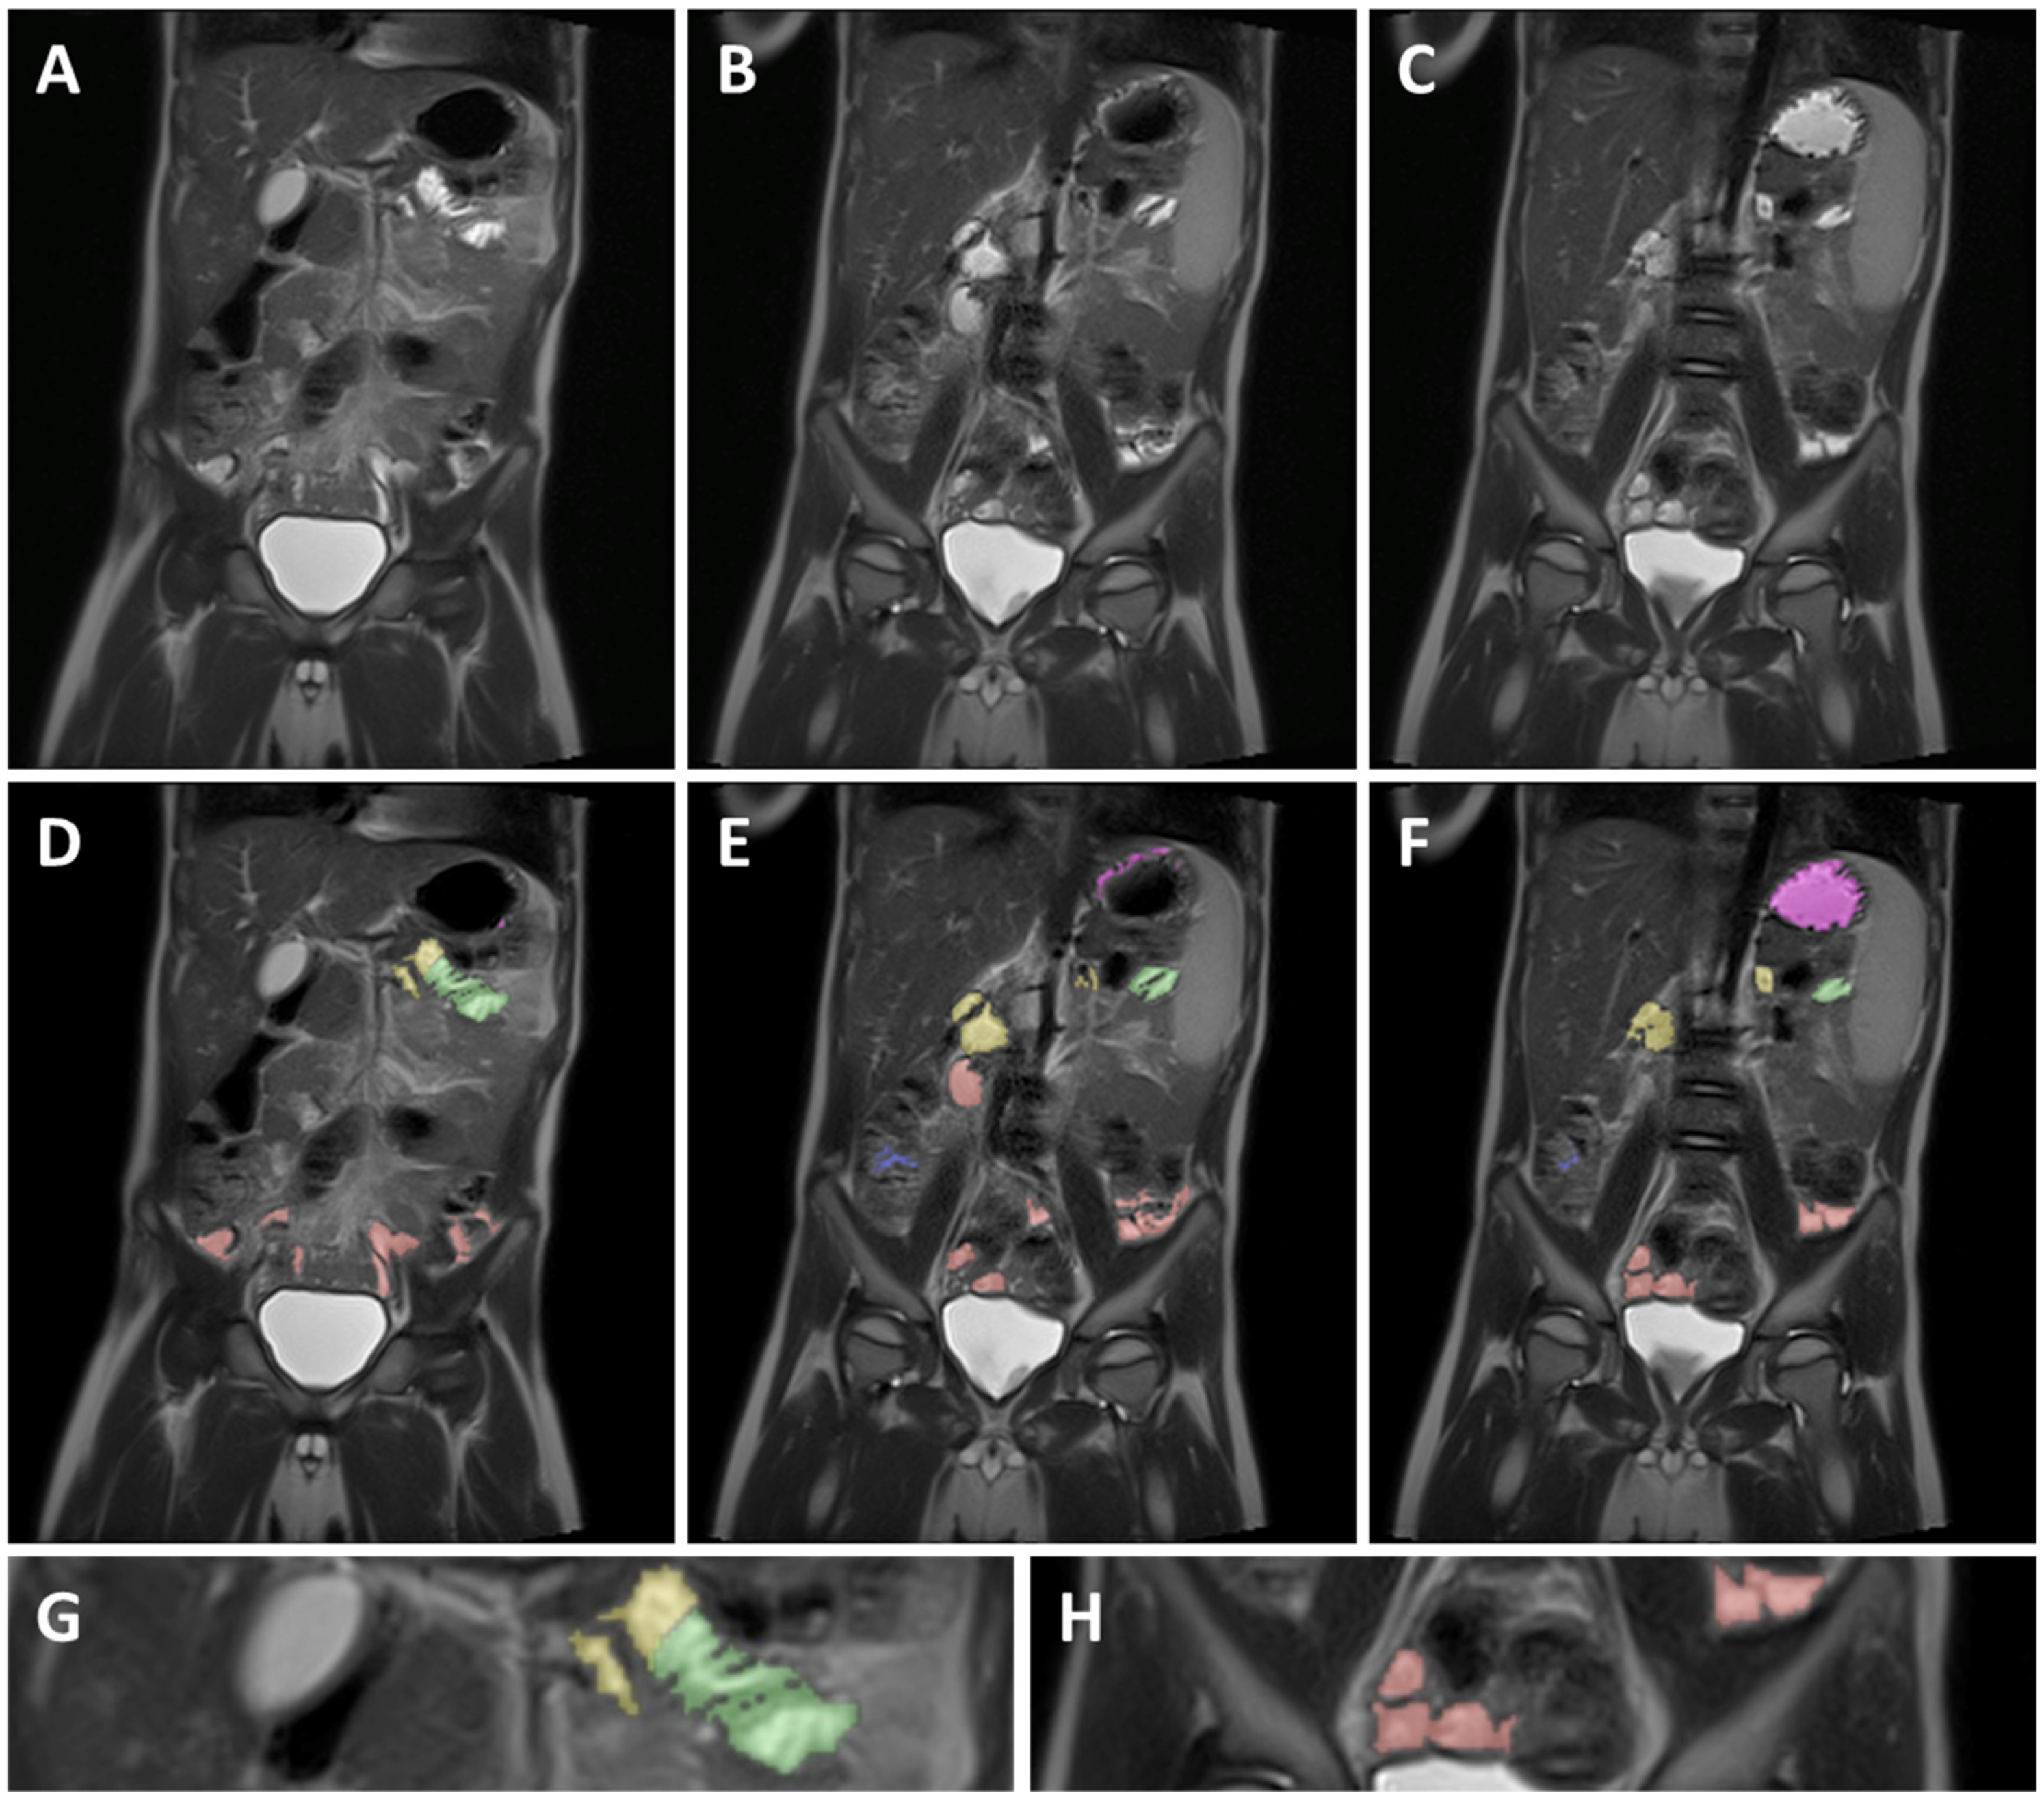

Figure 2.

Example of MRI identification of fluid pockets in different GI segments on 3 coronal T2 weighted spin echo images of a 5-year-old child. (A–C) are unmarked images; (D–F) are the corresponding marked images. Purple marked areas are located in the stomach, yellow in the duodenum, green in the jejunum, red in the ileum, and blue in the colon. (G) is a detailed view of the jejunum (green), showing the circular folds as the typical striped pattern in the fluid pocket. (H) is a detailed view of the ileum marked in red, showing the smooth intestinal wall.

As commonly accepted, the jejunum starts at the ligament of Treitz [27]. The end of the jejunum and transition to the ileum, however, is hard to define precisely using MRI imaging [27]. Consequently, the morphology and relative position in the abdominal cavity was used to differentiate between the jejunum and ileum. Morphological differentiation was based on the valvulae conniventes. Due to the closely spaced circular folds and the consequently thicker intestinal wall, the jejunum can be identified by a typical striped pattern in the GI fluid [27] (Figure 2G). In addition, the jejunum is mainly located in the top left quadrant, sometimes extending into the bottom left quadrant of the abdomen, while the ileum is mainly located in the bottom right quadrant, sometimes extending into the bottom left quadrant.

2.4.4. Ileum

Contrary to the jejunum, the ileum has less closely spaced circular folds [27] (Figure 2H). Consequently, the ileum can be identified by a smoother lined and thinner intestinal wall compared to the jejunum. The ileum ends with the ileocecal valve located at the start of the well-defined and easily localized colon.